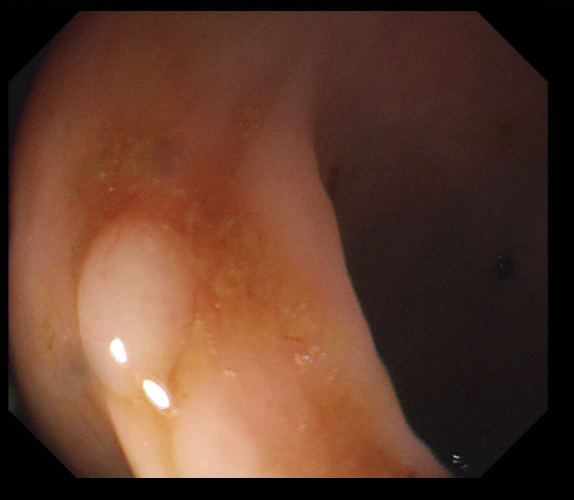

Early polyp segmentation was based in the texture and shape of the polyps. For example, Hwang et al. [8] used ellipse fitting techniques based on shape. However, some corectal polyps can be small (5mm) and are not detected by these techniques. In addition, the texture is easily confused with other tissues in the colon as can be seen in Figure 2.

With the rise of convolutional neural networks (CNNs) [10] the problem of the texture and shape of the polyps was solved and the accuracy was substantially increased. Several authors have applied deep convolutional networks to the polyp segmentation problem. Brandao et al. [2] proposed to use a fully convolutional neural network based on the VGG [16] architecture to identify and segment polyps. Unfortunately, the small datasets available and the large number of parameters make these large networks prone to overfitting. Zhou et al. [22] used an encoder-decoder network with dense skip pathways between layers that prevented the vanishing gradient problem of VGG networks. They also significantly reduced the number of parameters, reducing the amount of overfitting. More recently, Chao et al. [3] reduced the number of shortcut connections in the network to speed-up inference time, a critical issue when performing real-time colonoscopies in high-resolution. They focused on reducing the memory traffic to access intermediate features, reducing the latency. Finally, Huang et al. [7] improved the performance and inference time by combining HarDNet [3] with a cascaded partial decoder [21] that discards larger resolution features of shallower layers to reduce latency.